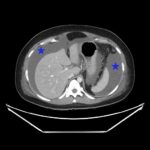

Ovarian hyperstimulation syndrome (OHSS) is a potentially life-threatening complication of assisted reproductive technology (ART). Here, we present the case report of a 30-year-old female undergoing infertility treatment who presented to the emergency department (ED) with nausea and vomiting, abdominal distention, and shortness of breath. On physical exam, she had notable ascites. Computed tomography (CT) of the abdomen and pelvis and pelvic ultrasound (US) revealed significant ascites and enlarged ovaries with multiple cysts. She was diagnosed with severe OHSS and admitted to obstetrics and gynecology (OBGYN) service for five days where she underwent intravenous (IV) hydration and paracentesis. This case report reviews the clinical presentation, categorization, management, and prevention of OHSS and provides examples of imaging findings consistent with the condition.